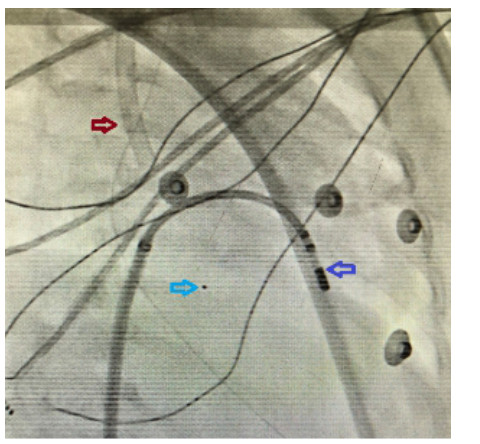

患儿在静脉-动脉ECMO(VA-ECMO)支持下持续发生室性心动过速,先后予胺碘酮13 µg/(kg · min)持续静脉泵注,维拉帕米13.3 mg Q8 h/Q6 h口服,西地兰0.1 mg静推,心率仍波动于170~200次/min之间。多学科会诊讨论后,诊断为:心律失常(室性心动过速);心源性休克;心动过速相关性心肌病;急性重症肺炎;心功能不全。予艾司洛尔负荷量5 mg静推3次,再予30~60 mg/h维持,心室率降至110次/min左右(图 2),患儿于2019-01-17在ECMO支持下行心电生理检查加射频消融术。操作过程:手术经右股静脉穿刺,在ECMO抗凝下给予肝素1 mg/kg。心率维持118~131次/min,血压维持在61/45 mmHg~88/80 mmHg之间,维持不理想,在ECMO运转下继续观察35 min,待患儿心率稳定于84次/min,血压103/86 mmHg,停ECMO运转。置入8F外鞘,导管依次进入右心房、右心室(图 3、4)。行术前电生理检查示:QRS宽大畸形,房室分离,室性心动过速,心率140。应用7.5 F蓝把费冷盐水大头消融导管,在三维标测系统(CARTO)标测下重建右心室激动顺序图,于间隔侧乳头肌处标测到最早双极电位提前QRS 15 ms,单极图呈QS型,且下降支有切记。温控法55℃,功率40 W放电10 s后心动过速即终止,巩固至180 s,观察20 min,未见心动过速发作。术中因ECMO系统形成的右心房负压对射频消融术的影响暂停ECMO 3次。患儿经ECMO支持下行射频消融术后心率、心律恢复正常,当日逐步停艾司洛尔静脉用药。术后第2天撤除ECMO,第4天撤离呼吸机。ECMO撤离1 d后出现室性早搏;撤离4 d后频发室性早搏,给予索他洛尔、普罗帕酮、卡托普利治疗心律失常。2019-01-22转入心血管内科,期间有间歇性心律不齐发作。2019-02-13再次出现室性心动过速,于外院救治。随访患儿情况,家属诉患儿循环稳定,再次行心电生理检查加射频消融术,恢复窦性心律,5 d后出院。

| 红色箭头所指管道为ECMO静脉插管;浅蓝色箭头所指为ECMO静脉插管未显影部分的末端标记显影点;深蓝色箭头所指为射频消融导管头端 图 4 导管入右室时的X线影像 |